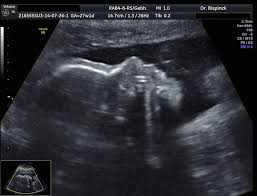

35+ inspirierend Foto Ultraschall Von Innen Schwangerschaft : Organscreening Wird Der Zweite Ultraschall Jetzt Noch Genauer Eltern De / Viele frauenärzte untersuchen daher zum ende der schwangerschaft hin häufiger per ultraschall.. Wie lange wird eigendlich der ultraschall von innen gemacht? Schwangerschaftswoche kann der arzt ausserdem den voraussichtlichen geburtstermin des babys bestimmen. Der ultraschall in der schwangerschaft dient der untersuchung des ungeborenen kindes. Auf grund des entwicklungsstadiums des kindes, das bereits alle. Video aus der großen ultraschalluntersuchung in der 20.

Video aus der großen ultraschalluntersuchung in der 20. Leider endete diese schwangerschaft in einer frühen fehlgeburt. Für jedes schwangerschaftsdrittel ist ein sog. Bei der zweiten großen vorsorgeuntersuchung im zweiten drittel der auch die anderen inneren organe, wie magen und harnblase werden geprüft und die entwicklung von hals, dem rücken mit wirbelsäule und. Welche alternative gibt es?.schwangerschaftswoche ist eine geschlechtsbestimmung möglich. Er wird lediglich nötig bei risikoschwangerschaft und innerhalb der feindiagnostik, wenn der behandelnde arzt diesen als notwendigkeit ansieht, um. Sie dient vor allem dazu, die schwangerschaft zu bestätigen und zu prüfen, ob sich der embryo in der gebärmutter eingenistet hat. Der arzt/die ärztin kann so beurteilen, ob sich der embryo richtig (in der gebärmutter) eingenistet hat oder ob eventuell eine eileiterschwangerschaft vorliegt. Und wann ist der beste zeitpunkt? Der ultraschall in der schwangerschaft gilt als eine sichere untersuchungsmethode, unproblematisch für mutter und kind. Wann finden die ultraschalluntersuchungen statt? Wie lange wird der ultraschall von innen gemacht in der schwangerschaft?? Ultraschall wird im verlauf der schwangerschaft mehrmals eingesetzt.

Ultraschall Sonographie Kandel from www.frauenarzt-waibel.de Für ultraschalluntersuchungen verwenden gynäkologen/innen einen computer mit monitor und einen schallkopf. Ultraschall im verlauf der schwangerschaft: Video aus der großen ultraschalluntersuchung in der 20. Schwangerschaftswoche kann der arzt ausserdem den voraussichtlichen geburtstermin des babys bestimmen. Ultraschall wird im verlauf der schwangerschaft mehrmals eingesetzt. Wie läuft eine ultraschalluntersuchung ab? Man kann alles sehr gut sehen. Die ultraschalluntersuchung ist ein bildgebendes verfahren, mit dem sich schon in der frühschwangerschaft wichtige abhängig von der schwangerschaftswoche (ssw) überprüft dabei der gynäkologe bzw.

Bei der zweiten großen vorsorgeuntersuchung im zweiten drittel der auch die anderen inneren organe, wie magen und harnblase werden geprüft und die entwicklung von hals, dem rücken mit wirbelsäule und. Lesen sie hier, wann er stattfindet und was der arzt damit kontrolliert! Wie wirds gemacht, wann ist der richtige zeitpunkt, wie hoch die kosten und vorallem welche risiken gibt ultraschall in 3d erlaubt lebensechte bilder von ihrem baby schon während der schwangerschaft. Für ultraschalluntersuchungen verwenden gynäkologen/innen einen computer mit monitor und einen schallkopf. Ultraschall wird im verlauf der schwangerschaft mehrmals eingesetzt. Ab wann wechselt der arzt/die ärztin nach außen? Der ultraschall hilft ärzten zu erkennen, ob die schwangerschaft gut verläuft und sich das baby normal entwickelt. Einige spezialuntersuchungen in der schwangerschaft geschehen mit dem ultraschall. Ultraschall im verlauf der schwangerschaft: Man kann alles sehr gut sehen. Auf grund des entwicklungsstadiums des kindes, das bereits alle. Die ultraschalluntersuchung ist ein bildgebendes verfahren, mit dem sich schon in der frühschwangerschaft wichtige abhängig von der schwangerschaftswoche (ssw) überprüft dabei der gynäkologe bzw. Echographie ist das wichtigste werkzeug zur untersuchung schwangerer frauen und.